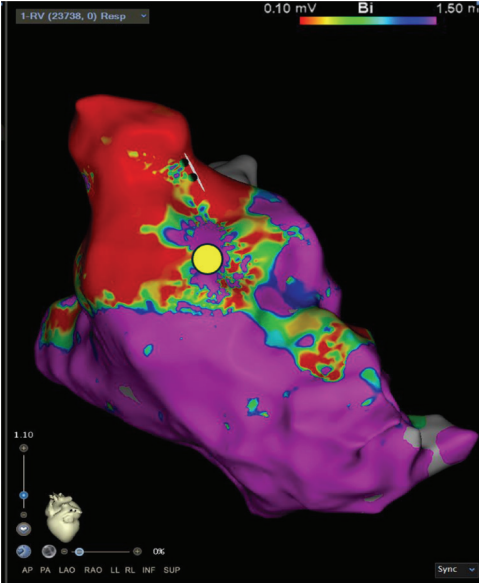

Substrate Mapping

A high-definition map was constructed with an Optrell catheter and RV pacing to better understand the patient’s surgical scar-based substrate before ventricular stimulation (Figure 1). The scar was noted almost exclusively in the RV outflow tract anteriorly stretching across to the tricuspid valve annulus. A small amount of patchy scar was noted in the anterior mid to apical RV as well; however, the septum did not have a significant scar near the predicted VSD Dacron patch. A slowly conducting anatomic isthmus (SCAI) with a conduction velocity of <0.5 m/s was marked (yellow circle, Figure 1). The conduction velocity cutoff of <0.5 m/s has been predictive of arrhythmogenic isthmuses in repaired Tetralogy of Fallot (rTOF).1,2 Preemptive ablation of identified SCAIs is associated with lower rates of VT and ICD implantations in the rTOF population.3 This heterogenous scar area was likely related to the prior RV infundibular muscle resection, surgical PVR 10 years prior, and valve-in-valve TPVR struts just 4 months prior that seemed to play a part in triggering their ventricular arrhythmias.

After examining the baseline voltage to identify surgical scar, SCAIs and functional substrate maps, a pacing catheter was then placed in the predicted VT isthmus (yellow circle, Figure 1). VT was easily induced with 2 extrastimuli off of isoproterenol. A single monomorphic tachycardia at a cycle length of 270 ms was induced originating from the RV (Figure 4A). Entrainment was performed from the catheter that was preemptively put into the isthmus at a cycle length of 250 ms, which successfully entrained the tachycardia. The post-pacing interval - tachycardia cycle length from this location was 38 ms with a small degree of manifest fusion and a stim to QRS that was extremely short (Figure 4B). We believe these findings were all consistent with the area of entrainment being in very close proximity to the exit of the tachycardia. An attempt at VT activation mapping was performed with the Optrell (Figure 5); however, this tachycardia was extremely poorly tolerated. Ablation was performed across this isthmus and within the scar followed by high-output pacing to confirm noncapture of ablated tissue. A ventricular stimulation protocol was performed with up to 3 extrastimuli from 2 locations in the RV on and off isoproterenol with noninducibility of ventricular tachyarrhythmias. At 7-month follow-up, the patient had no further VT on the same dose of dofetilide that he was previously on for atrial tachyarrhythmias.